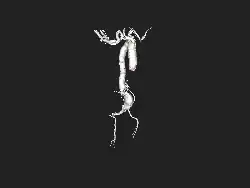

![]() | |

| Angiography of an aneurysm in a brain artery. The aneurysm is the large bulge in the center of the image. | |